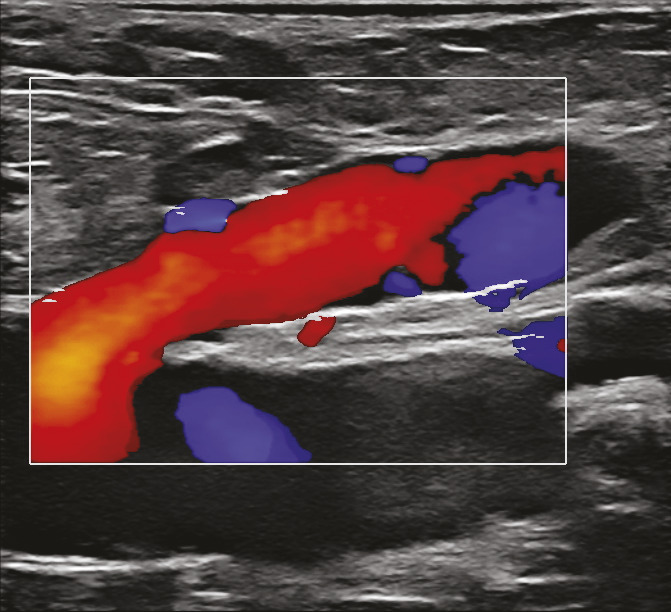

L’écho-Doppler couleur fournit une image des flux qui se superpose à l’image échographique. Cette technique permet d’analyser le sens d’écoulement des flux et leur vitesse de façon semi-quantitative. Par convention, les flux qui se dirigent vers la sonde échographique sont colorisés en rouge et ceux qui fuient la sonde échographique en bleu. Dans les veines saines, le bon fonctionnement du système valvulaire n’autorise qu’un écoulement antérograde en direction du cœur (colorisé en bleu compte tenu de l’orientation de la sonde échographique) dans le système veineux superficiel et profond. Du fait de l’incompétence valvulaire dans les veines variqueuses, on observe, après mobilisation de la colonne sanguine dans le sens antérograde, un reflux colorisé en rouge (fig. 14).